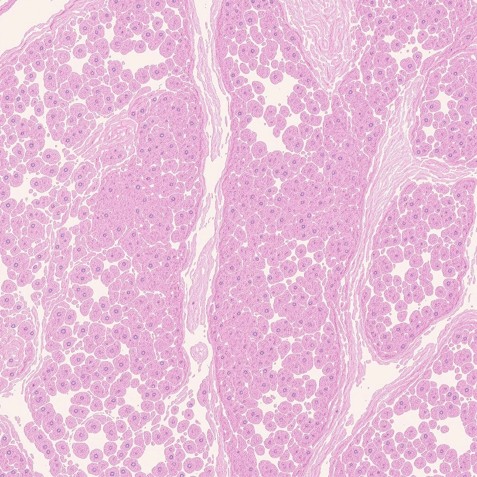

SK Node Slovakia role: Collecting, processing screening data